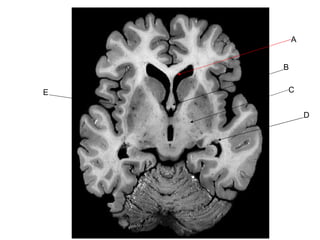

A B C D E

Answer Key A: lateral ventricle B: fornix C: posterior limb of internal capsule D: caudate nucleus E: insula